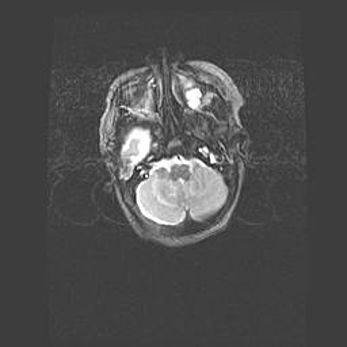

Подострая гематома правой гемисферы мозжечка.

Наружная гидроцефалия.

Возраст: 15 дней

Вес: 3100 г

Пол: женский

Окружность головы: 37 см

Срок гестации: 35-36 недель

При открытой наружной форме гидроцефалии у новорожденных расширяются и переполняются субарахноидные пространства.

Кровоизлияния в мозжечок имеют две клинико-анатомические формы: полушарные гематомы и кровоизлияния в червь.

К появлению этой патологии может привести: повреждения головного мозга, возникающие в результате асфиксии и гипоксии плода при беременности, или травмы во время родов. Редко гематома мозжечка может быть результатом первичной коагулопатии и сосудистой мальформации, диссеминированном внутрисосудистом свертывании, изоиммунной тромбоцитопении.